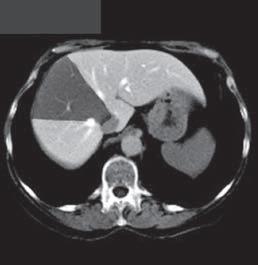

Kazuistika I (segmenty jaterní tkáně)